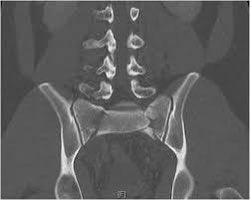

@radRounds Probably vertical shear pelvic injury. İt may be bilateral transforaminal or U/H type sacral fracture